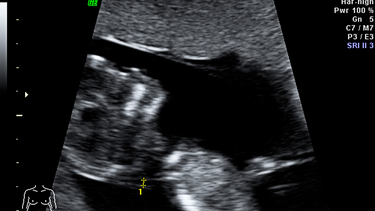

Thai chưa vào tử cung siêu âm đầu dò có thể không thấy vì nếu thai chưa làm tổ trong tử cung, dù thử thai 2 vạch, bác sĩ vẫn chưa thể quan sát thấy túi thai qua hình ảnh siêu âm đầu dò. Đây là tình trạng phổ biến và hoàn toàn bình thường trong những ngày đầu của thai kỳ. Do đó, chị em không nên quá lo lắng nếu chưa thấy hình ảnh túi thai ngay lần siêu âm đầu tiên.

Siêu âm đầu dò là kỹ thuật hình ảnh hiện đại, cho phép bác sĩ quan sát rõ ràng hơn bên trong tử cung và các cơ quan sinh sản. Phương pháp này giúp xác định vị trí làm tổ của thai nhi, kiểm tra sớm các dấu hiệu bất thường như mang thai ngoài tử cung hoặc dọa sảy thai.

Tuy nhiên, trong 3 tuần đầu sau khi thụ tinh, phôi thai còn rất nhỏ và đang trong giai đoạn di chuyển để làm tổ trong tử cung. Thời điểm này, siêu âm đầu dò thường chưa thể phát hiện túi thai, bởi túi phôi vẫn chưa ổn định vị trí. Đó là lý do vì sao bác sĩ thường khuyên mẹ bầu nên chờ đến tuần thai thứ 5 trở đi mới nên siêu âm để xác định chắc chắn thai đã vào tử cung hay chưa.

Từ tuần thứ 5, phôi thai bắt đầu hình thành rõ nét hơn, kích thước cũng đủ lớn để nhìn thấy qua hình ảnh siêu âm đầu dò. Nếu siêu âm vào thời điểm này, bác sĩ có thể đánh giá vị trí và sự phát triển ban đầu của thai nhi, từ đó phát hiện kịp thời nếu có bất thường xảy ra.

Siêu âm đầu dò qua đường âm đạo

Đây là phương pháp siêu âm có độ nhạy cao, cho phép quan sát được hình ảnh túi thai từ tuần thai thứ 4 – 5. Nếu siêu âm chưa thấy gì trong buồng tử cung, bác sĩ có thể khuyên bạn đợi thêm vài ngày rồi siêu âm lại để có kết quả rõ ràng hơn.